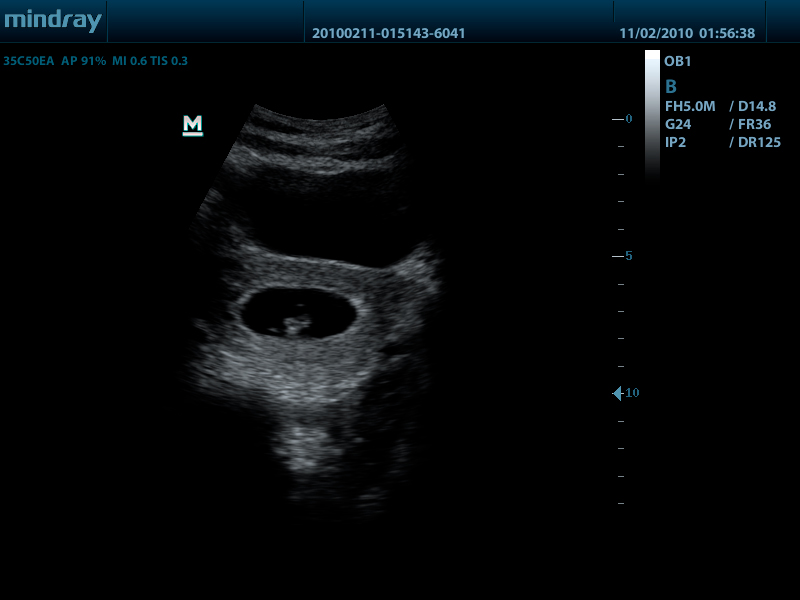

Mindray DP-50 – портативная цифровая ультразвуковая система с ЖК монитором 15 дюймов (1024Х768)

и встроенными аккумуляторными батареями (опция) позволяющими работать в автономном режиме до 2-х часов.

DP-50 – портативный УЗИ сканер разработан на базе новой платформы X-treme engine, используемой в хорошо зарекомендовавших себя цветных сканерах с доплером моделей DC-3, DC-7, DC-6. Эта платформа открывает возможности для расширений до уровня цветных сканеров и совместимости с широким диапазоном периферийного оборудования. X-treme означает интеллект, высокую скорость обработки данных, многоуровневую передачу сигналов, а также возможность оптимизации изображения и модульного расширения.

Применяемые датчики DP-50:

Конвексный датчик 35C50EA (2.0/3.5/4.5/5.0/Н5.0/Н6.0) R50